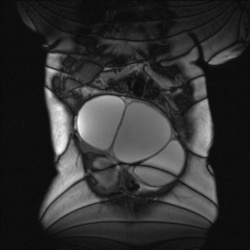

10.07.2014 - 18:56

Женщина, 1938 г.р. Жалобы на запоры, боли внизу живота, увеличение живота. Вопрос-уточнение - образование ведь из яичника идет? Первичное или вторичное (левый яичник тоже изменен)? Контрастирование...